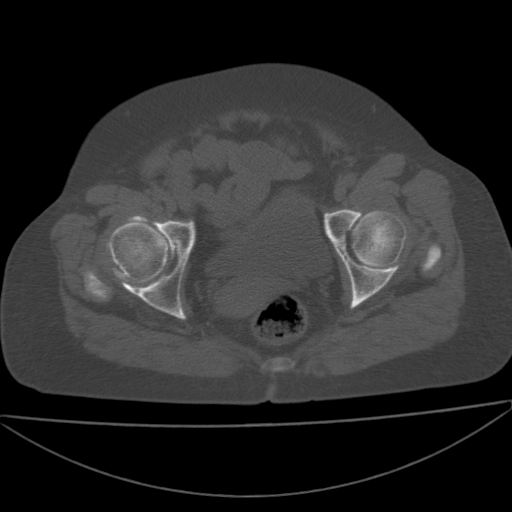

以下是引用余辉在2009-4-23 17:08:00的发言:[br]考虑右髋关节退行性变.股骨颈改变考虑陈旧性骨折可能,股骨头顶部关节面下似有透亮区,股骨头皮质环增厚,考虑有股骨头坏死

以下是引用王显瑞在2009-4-23 16:45:00的发言:[br]考虑股骨颈陈旧性骨折,股骨头缺血型坏死